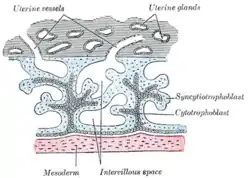

- Floating villi float freely in the intervillous space. They exhibit a bi-layered epithelium consisting of cytotrophoblasts with overlaying syncytium (syncytiotrophoblast).

| Primary | The chorionic villi are at first small and non-vascular. | 13–15 days | trophoblast only[1] |

| Secondary | The villi increase in size and ramify, while the mesoderm grows into them. | 16–21 days | trophoblast and mesoderm[1] |

The bulk of the villi consist of connective tissues that contain blood vessels. Most of the cells in the connective tissue core of the villi are fibroblasts. Macrophages known as Hofbauer cells are also present.